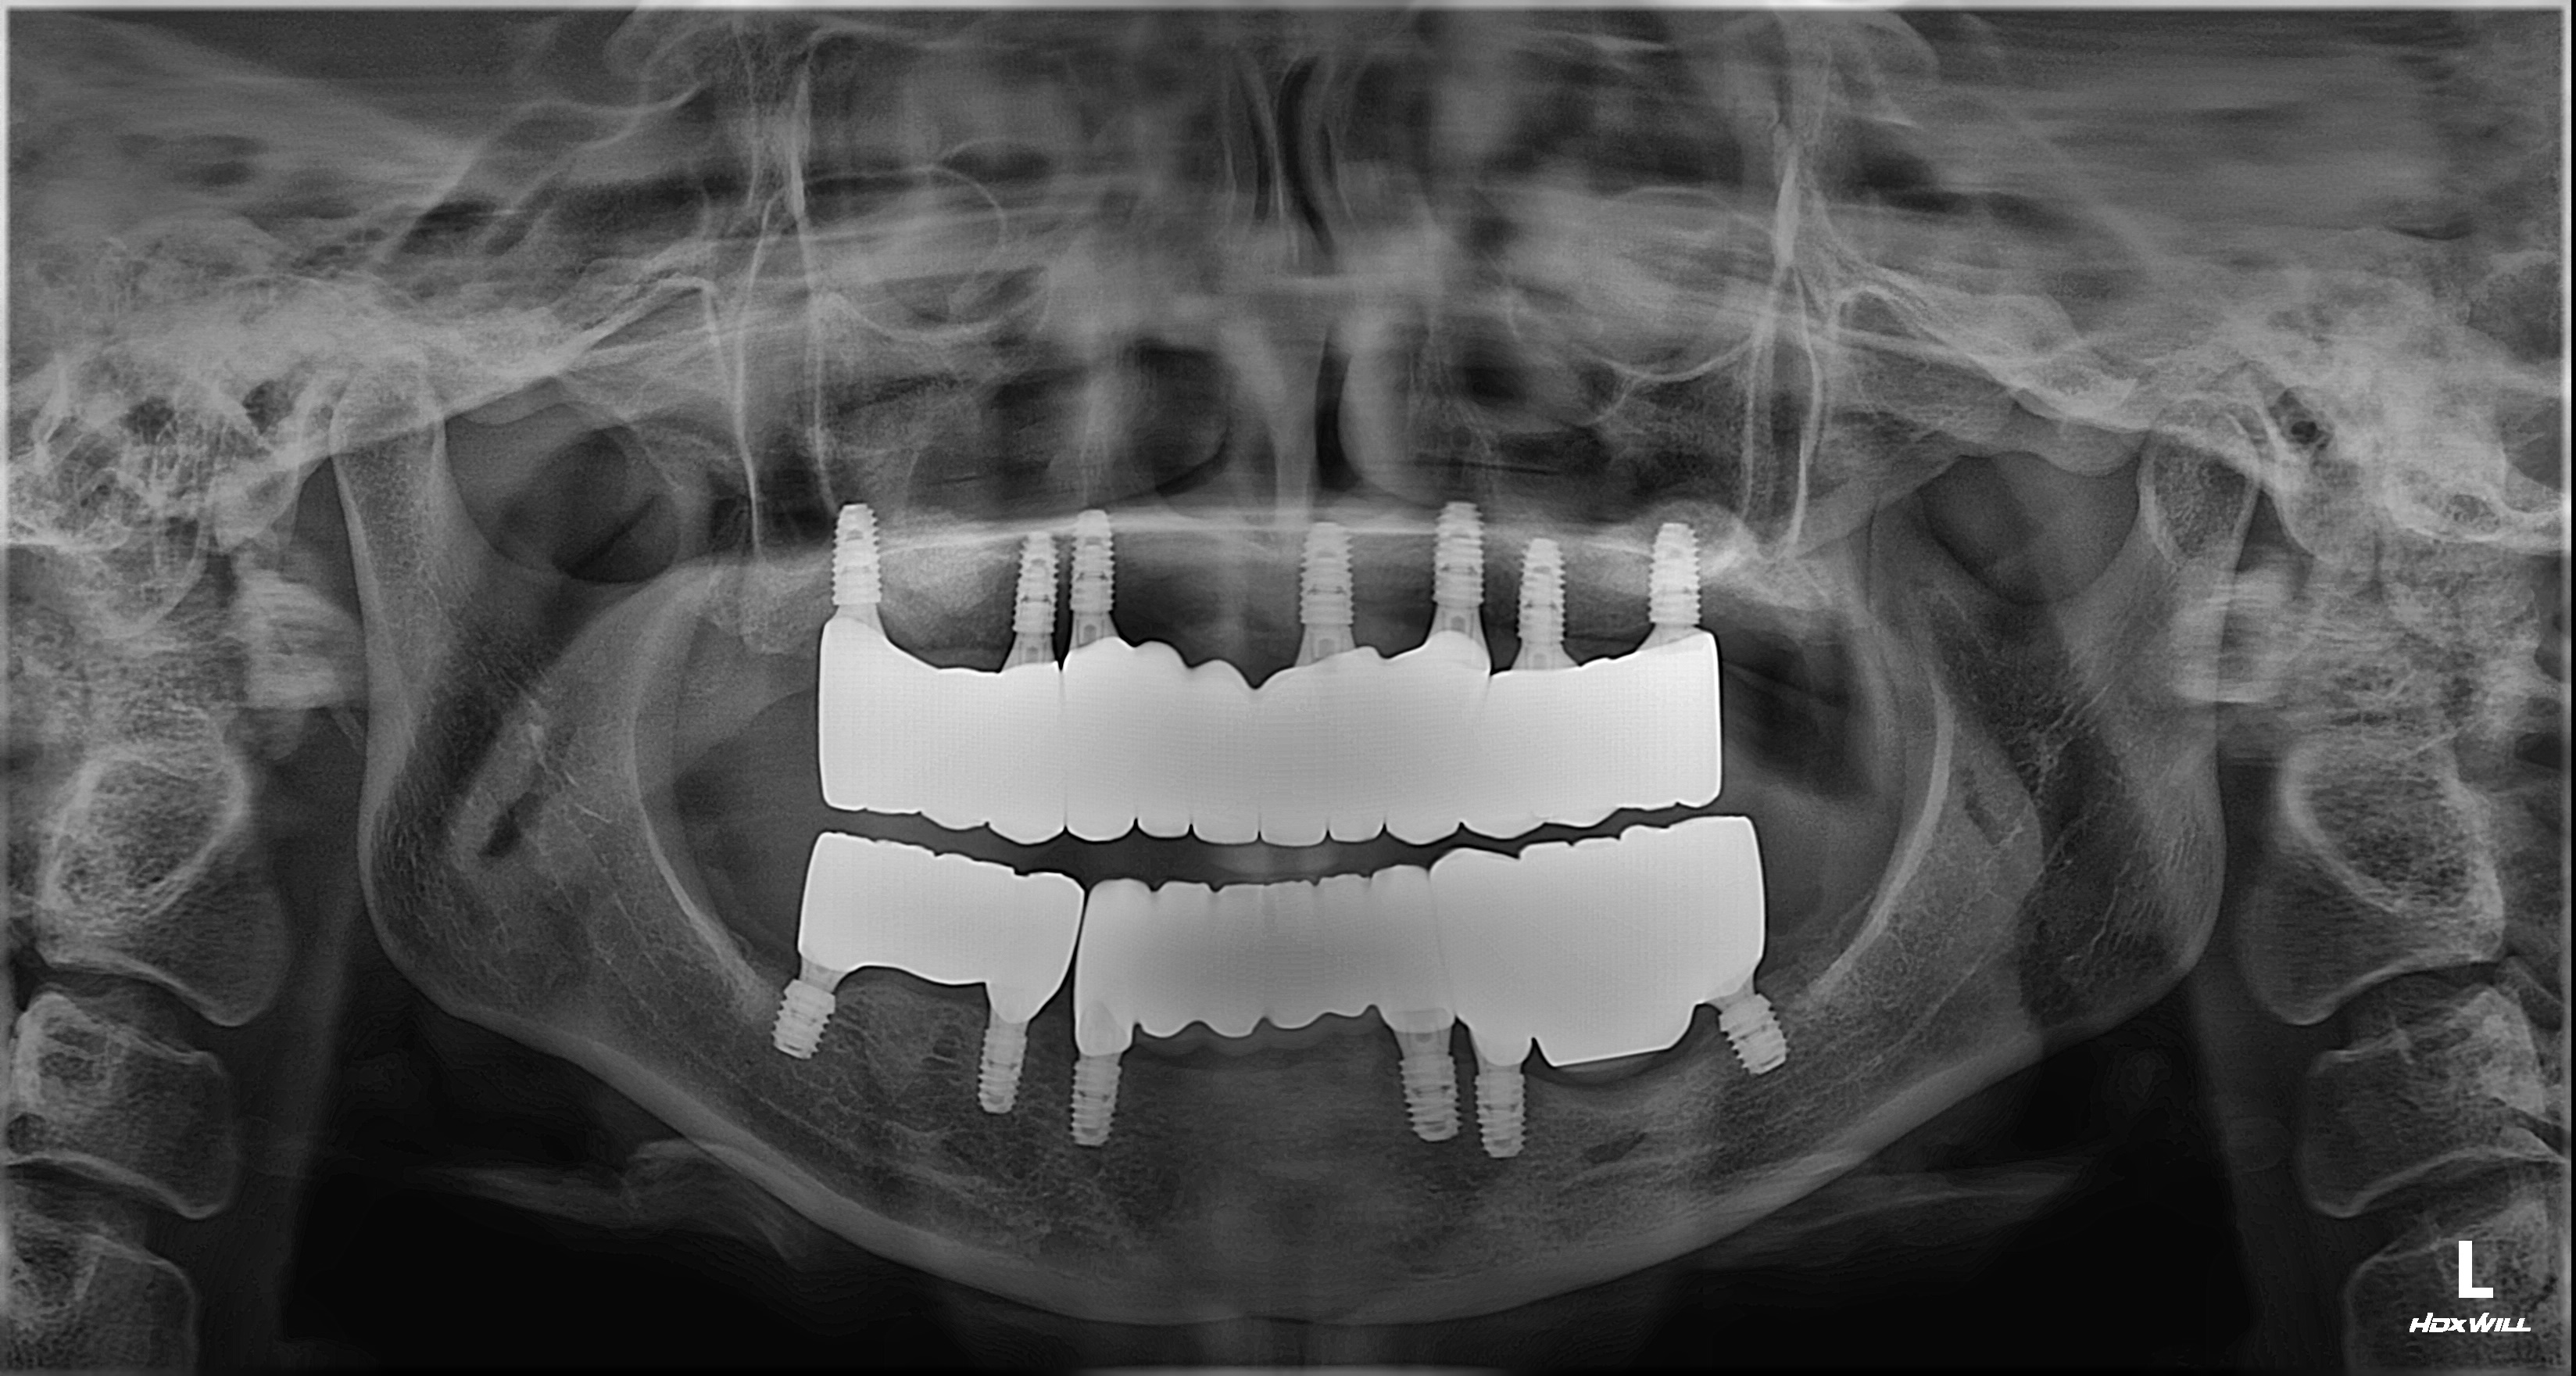

촬영일시: 2025.02.19 [ 치료기간: 2024년 05월 02일 ~2025년 02월 19일 ] ※ 365서울앞선치과의원의 모든 컬럼은 각 진료과 의료진이 직접 작성합니다. 365서울앞선치과의원 임상 케이스 게시물은 환자분께 의학적으로 정확하고 상세한 정보를 드리기 위해 각 진료과 의료진이 직접 작성하며, 모든 증례 사진은 본원 의료진이 직접 시술한 증례를 촬영한 것으로, 의료법 제23조, 제56조에 의거하며 환자분의 동의를 얻어 포스팅에 사용하였습니다. 또한 해당 케이스는 본 환자분의 치료 결과이며, 환자 상태에 따라 치료의 결과는 달라질 수 있습니다. |